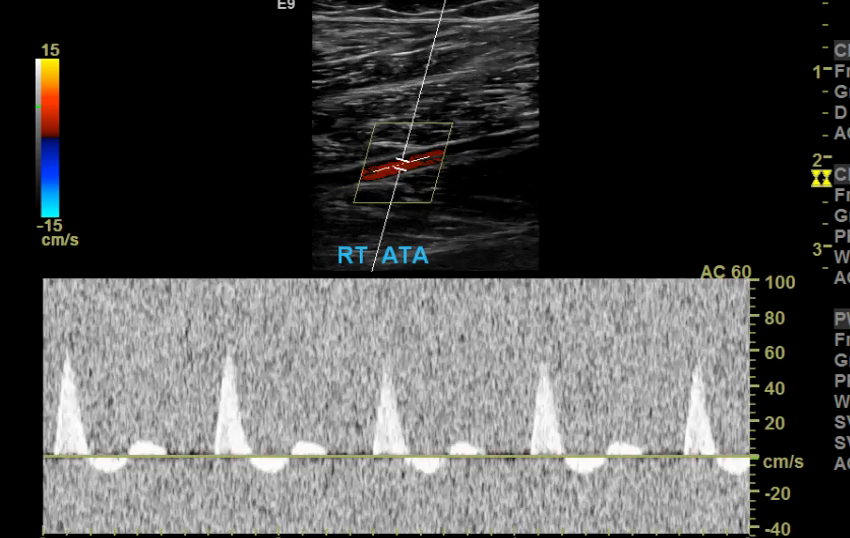

Too low of a scale and you’ll get aliasing which makes getting a proper velocity impossible.

Scale/PRF too low

Aliasing from low PRF